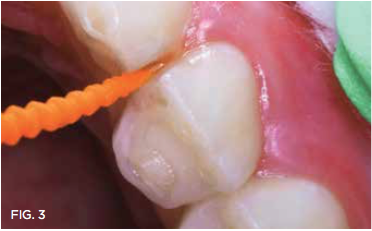

Case 1. A 9-year-old girl had a distal caries lesion of the primary canine tooth and mesial caries of the approximating primary first molar (Figure 1). With no local anesthesia and no discomfort reported by the child, a high-speed diamond bur was used to trim open the contact, exposing the lesions (Figure 2). After the site was air-dried, a flexible interdental pick was used to apply the SDF solution (Figure 3), which was blotted dry with a cotton swab after 60 seconds (Figure 4).

Fig 3. SDF applied with  exible proximal pick.

Fig 3